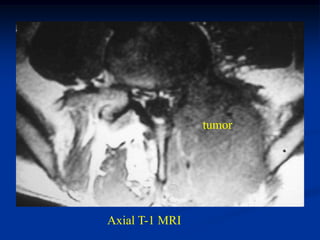

Case #1096

18 year male with

adamantinoma tibia

Bone scan

Sagittal T-2 MRI

Axial T-2 MRI